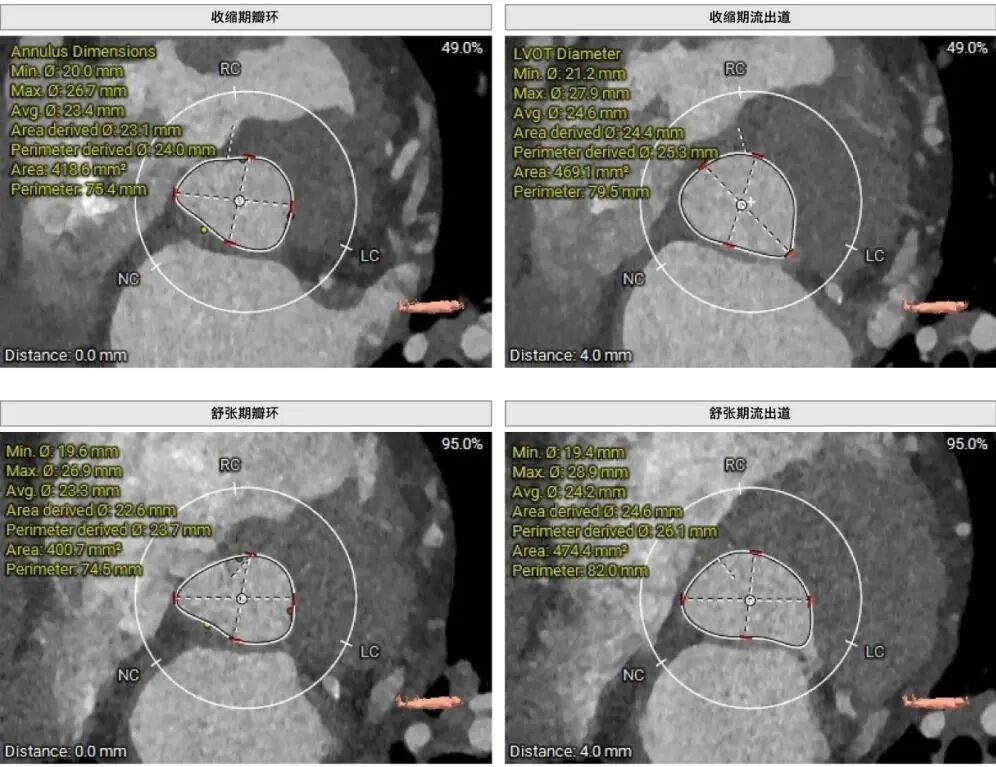

高龄患者,因“反复胸痛2年,加重伴气促1周”入院,超声心动图提示主动脉瓣极重度狭窄(图A),主动脉CT提示三叶式主动脉瓣,瓣叶增厚,重度钙化,L-R钙化高位粘连(图B),患者已有心源性休克、晕厥的表现,病情危重,更为棘手的是,患者同时存在反复消化道出血,经多学科会诊,明确诊断为海德综合征(Heyde综合征)——一种因主动脉瓣狭窄导致胃肠道血管发育不良继而引发出血的严重并发症。

B:主动脉根部CT分析:三叶式主动脉瓣,瓣叶增厚,重度钙化,L-R钙化高位粘连